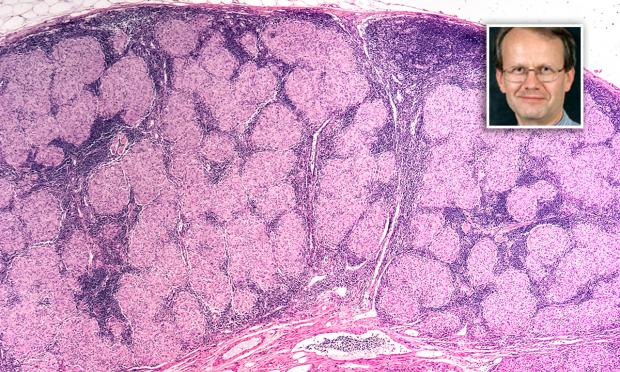

Vol 208, Issue 8: 7 May 2018. Professor Paul Thomas is a consultant respiratory physician at the Prince of Wales Hospital in Sydney. He discusses the diagnosis and management of sarcoidosis. With MJA news and online editor, Cate Swannell.